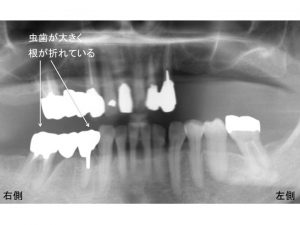

次に下顎右側の奥歯ですが、

この奥歯のブリッジ部ですが、

ここも歯が大きく虫歯になっていたり、根が折れている状態です。

同部も抜歯が必要な状態です。

しかし、同部を抜歯してしまうと左右側の奥歯で噛めなくなってしまいます。

そのため、下顎右側は、現状では抜歯せずに

まずは、上顎左側の治療を先行させて行うことになりました。

そして、左側で噛むことや審美的なことが達成されてから

下顎右側を抜歯し、インプラント治療を行うことになりました。